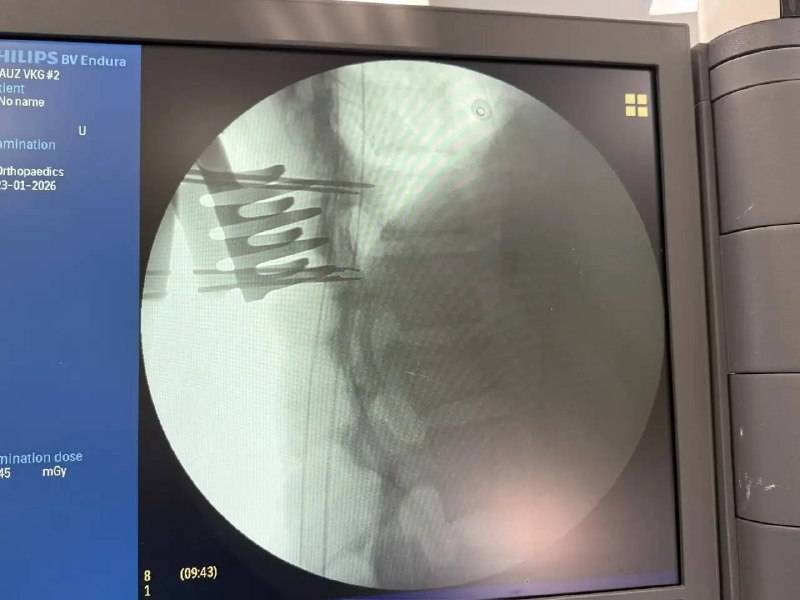

19 января во Владивостокскую клиническую больницу №2 из Арсеньева была экстренно доставлена молодая девушка с тяжёлой травмой — компрессионным переломом позвонка со стенозом позвоночного канала. Перелом сопровождался сдавливанием спинного мозга, что привело к парезу ног и нарушению функций тазовых органов.

После предоперационной подготовки нейрохирурги провели сложную четырёхчасовую операцию. Врачи устранили компрессию спинного мозга и стабилизировали позвоночник металлоконструкцией, предотвратив риск необратимых последствий. «Ключевую роль сыграло именно оперативное вмешательство. Мы сняли давление со спинного мозга и уже на вторые сутки начали раннюю реабилитацию», — отметил заведующий 1-м нейрохирургическим отделением Дмитрий Захаров.